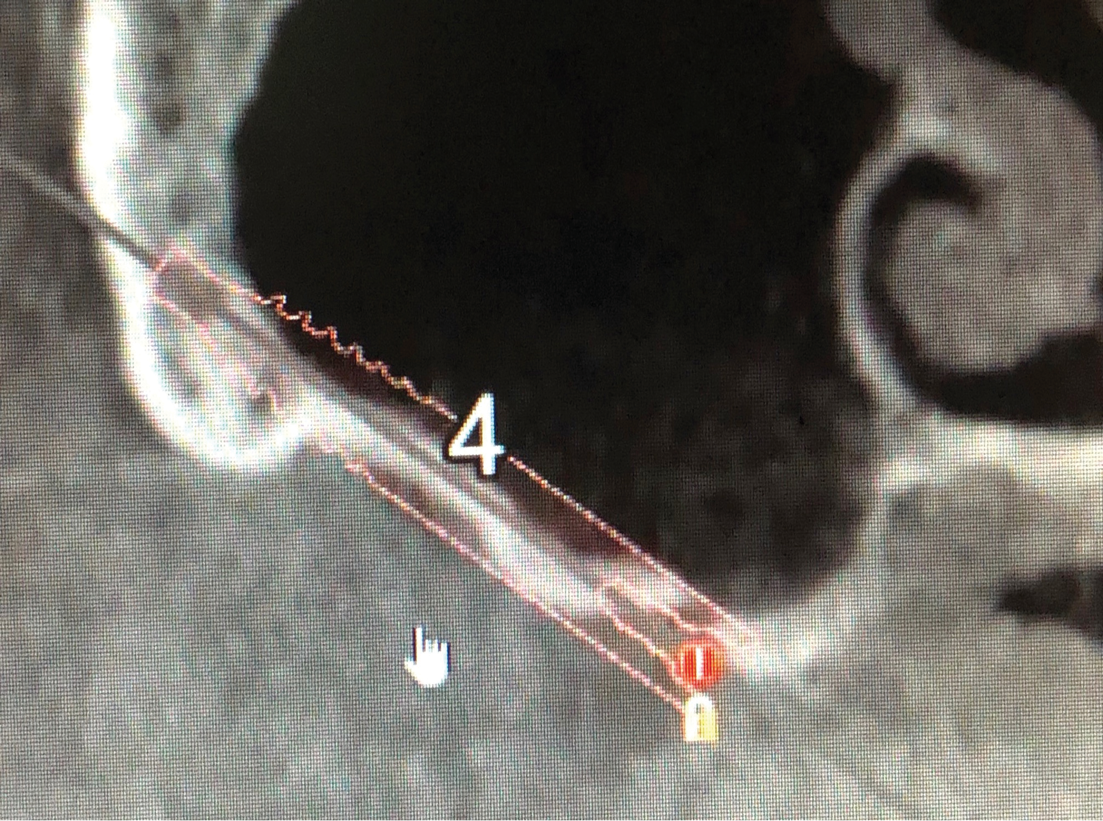

So, where can clinicians who have decided that they might want to add these clinical treatments to their patient offerings acquire the necessary education and training, and what should the training path be? Initially, online resources can be helpful. There are many YouTube videos and recordings of webinars available from global educators. Next, clinicians should consider courses in which various models are used in order to learn the positioning and angulation of the implants and handpiece (Figure 4). Proper angulation is critical for the positioning of both zygomatic and pterygoid implants. When clinicians are ready for hands-on training, they should seek out courses involving human cadavers, which include needed anatomy and treatment planning didactics, model workshops, and intensive, interactive, supervised cadaver workshops. Although these courses have trained many very interested and talented clinicians to place these implants, anecdotally, as many as half of the initial placements performed by students require either a subtle or major reorientation in positioning. Therefore, the need for hands-on training prior to treating patients cannot be overemphasized.

(4.) Demonstration model from a hands-on workshop. Note the crest cradle or channel and the posterior zygomatic implant, which required a reorientation due to an initial position that was too facial.

Figure 4